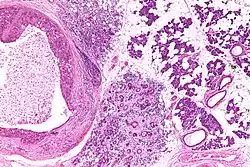

Low magnification micrograph of a salivary duct carcinoma with characteristic comedonecrosis (left of image) adjacent to normal parotid gland (right of image). H&E stain.

Salivary duct carcinoma (SDC) is a rare type of aggressive cancer that arises from the salivary glands.[1] It is predominantly seen in men and, generally, has a poor prognosis.[2] Other high grade carcinomas can mimic SDC. About 40-60% of SDC arise in pleomorphic adenomas.[3] Most, if not all, SDCs express androgen receptor by immunohistochemistry.[4] Therapeutically relevant genetic alterations include ERBB2/Her2 amplification, PIK3CA and/or HRAS mutations.[5][6]

Their histologic appearance is similar to ductal breast carcinoma.